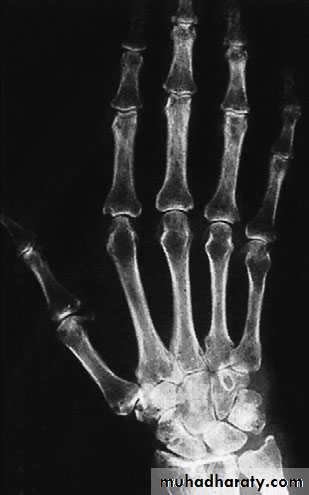

RHEUMATOID ARTHRITIS

X-ray:

most common sites:(MCP) joints, the wrists and

distal (RA) jointsPATHOLOGY:

Synovitis of the joints and tendon sheaths

the disease joints become eroded

attenuation of the ligaments and tendons

instability and progressive deformity

tendon rupture

Clinical features:

Stiffness and swelling of the fingers

carpal tunnel compression

swelling of the MCP and PIP joints, giving the fingers a spindle shape;

Bilateral symmetrically.

The joints are tender and crepitus may be felt on moving the tendons.

grip strength are diminished.

Early deformity : slight radial deviation of the wrist and ulnar deviation of the fingers, correctable swanneck deformities of some fingers, an isolated boutonnière or the sudden appearance of a drop-finger or mallet thumb (from extensor tendon rupture).

Late deformity: the carpus settles into radial tilt and volar subluxation; there is marked ulnar drift of the fingers and volar dislocation of the MCP joints, often associated with multiple swan-neck and boutonnière deformities.